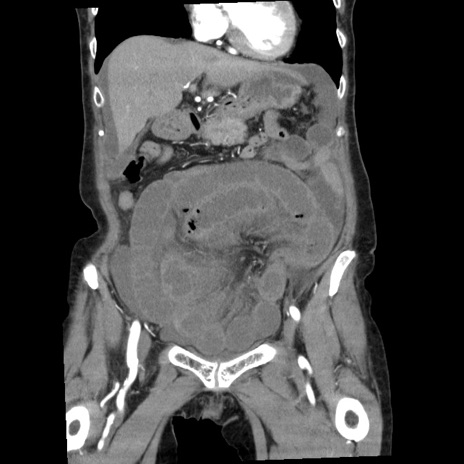

症例1(冠状断像)

【症例】80歳代女性

【主訴】腹痛

【現病歴】8時間前から腹痛あり来院。

【既往歴】糖尿病、脂質異常症、子宮体癌にて子宮全摘術

【身体所見】意識清明・会話良好だが腹痛で苦悶様、全腹部にわたって反跳痛と圧痛あり

【データ】WBC 13600、CRP 0.14、LDH 224、CK 90